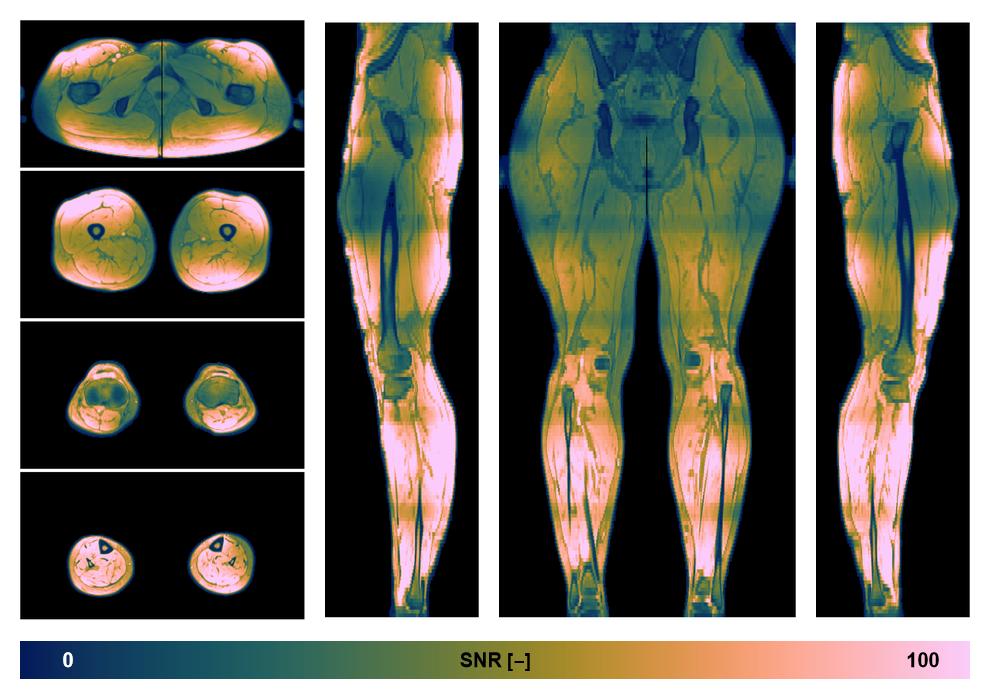

• SNR distribution

The SNR distribution of the dixon data.